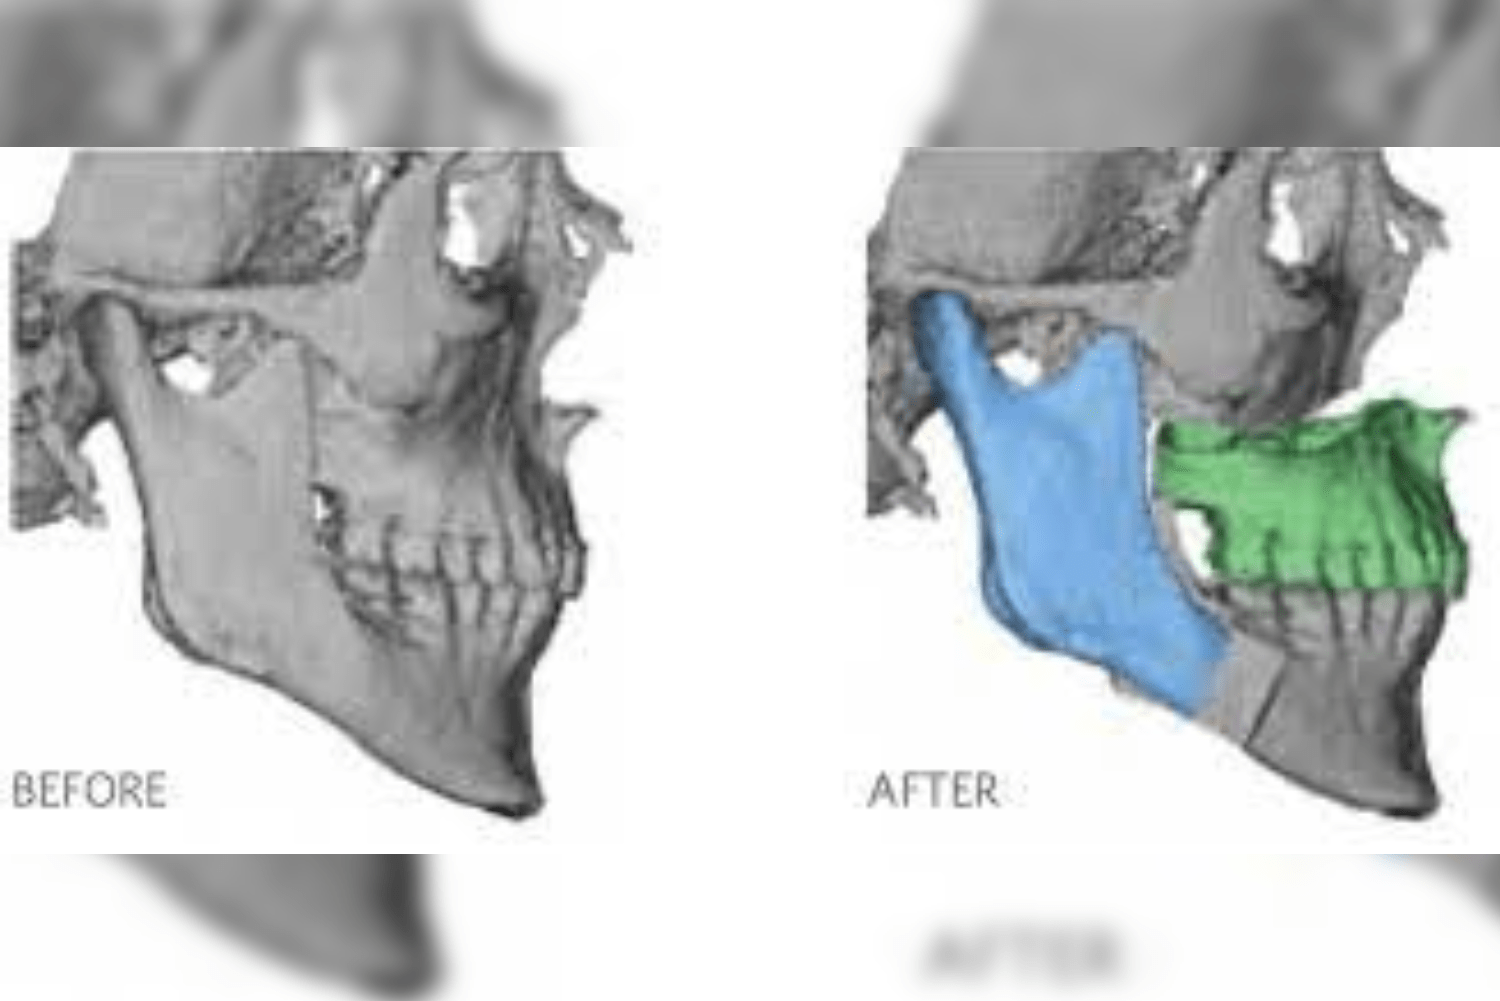

Straighten crooked teeth with orthodontic management:

- The crooked teeth are one among the reason for getting cavities. As

there are no self-cleansing area in between the teeth of crooked case,

the chances of food lodgement and getting caries is more. - So, its advisable to do the orthodontic treatment for straightening of the

teeth which can reduce the chances of getting cavities.Or in that case, its advisable to do the cleaning by dentist for every six

months is mandatory.